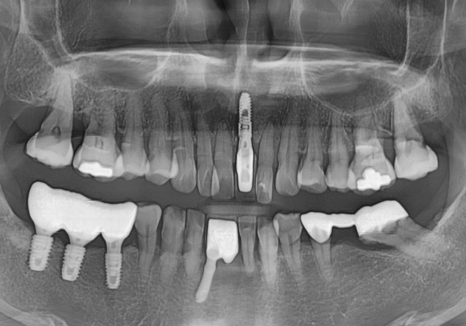

방사선 사진상,

치아 뿌리끝 염증도 진행되었고

뼈가 녹아 흔들림도 있던 상태라

231107 뿌리 끝 염증으로 뼈가 녹은 모습

발치 후 임플란트 방향으로

계획을 잡았습니다.

방사선 사진상, 뿌리끝 염증으로

뼈가 녹은 부위가 있었고,

뼈 폭도 얇아 임플란트만 식립하기엔

무리가 있어 보였습니다.

231107

그래서 뼈이식과 함께

임플란트 수술을 진행하는 것으로

계획을 세웠습니다.